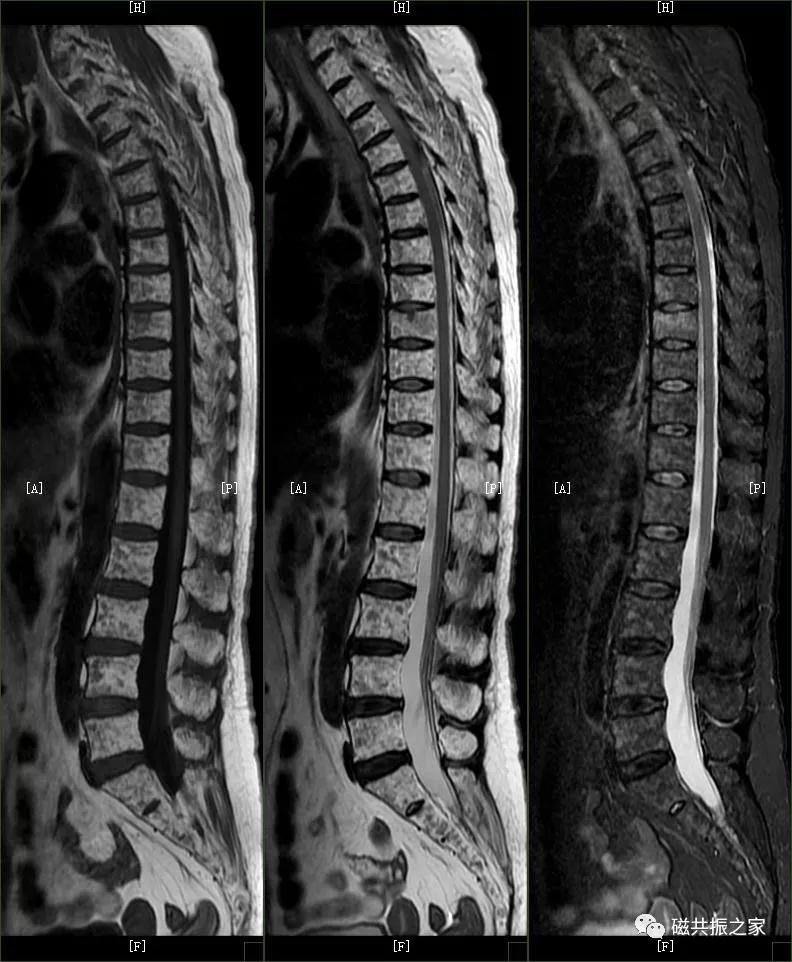

腰椎由5个椎体组成,生理曲度略向前,椎体体积较大,椎体的MR信号与椎体内的骨髓成分相关,椎体内的松质骨主要是脂肪成分,在T1WI上呈中/等信号,在T2WI成高信号;致密的骨皮质在T1WI、T2WI均呈低信号。腰椎常规扫描SAG FSE T1WI、SAG FSE T2WI、SAG STIR,及AX T2WI序列(脊髓内灰质病变可用MEDIC序列,了解神经根可进行稳态进动序列的神经根成像),如脊柱侧弯,椎管占位及了解椎体附件等需加扫冠状位。